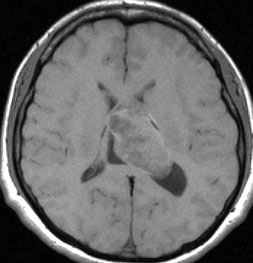

無症状で偶然発見された38歳女性の症例

central neurocytomaが透明中隔 septum pellucidum から発生していることがよくわかる症例です。症状はありませんでしたが,この腫瘍がこのままのサイズで留まることはあり得ないので手術摘出を勧めました。これ以上大きくなると手術にしても放射線治療にしてもリスクが大きくなりすぎます。脳弓にくっつくので脳弓損傷を避けるのが手術のポイントです。脳室壁にくっつくのですが剥がしていけば取れますが,大きな上衣下静脈 large subependymal vein の損傷には注意を払います。

手術後の画像です。脳神経外科の先生は手術根 surgical track に注目して下さい,左頭頂葉皮質切開 transcortical approachで手術を行っています。このルートでは全く手術後の神経脱落症状が出ませんでした。central neurocytomaの手術方法は,上記に加えて前頭葉皮質切開でまっすぐ前角に入る方法と経脳梁法 transcallosal approachがあります。経脳梁法は限られた小さめの腫瘍にしか応用できません。anterior callosal approach以外ではdisconnection syndromeが出るからです。central neurocytomaは脳室の壁にベトベトくっつくし,anterior callosal approachでは脳室壁の観察はかなり限られるからです。大きなものでは必ず経皮質法を選択して下さい。